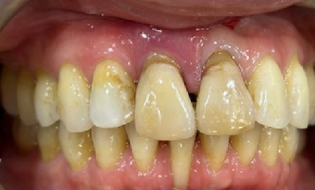

Before

- When patient was a teenager, both #8/#9 tooth fell out of socket

- Dentists did root canals on both teeth extraorally and re-inserted into socket

- #8 root horizontal fracture

- Both u1s showed root resorption

- HTE: #8 horizontal root fracture at bone level

- Failed root coverage surgery on #25